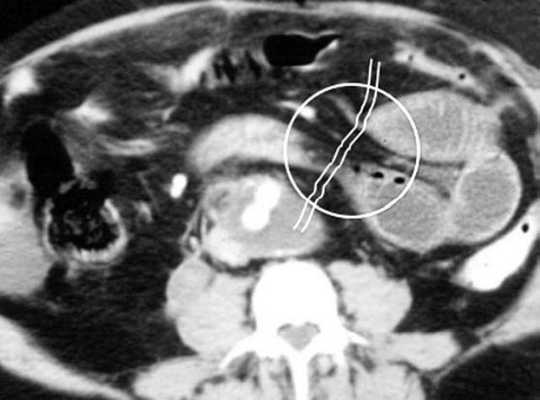

(г, д) На рентгенограммах выявлен симптом «штопора» — спиральная конфигурация 4-го отдела двенадцатиперстной кишки и проксимальной части тощей кишки.

Перекручивание тонкой кишки, приводящее к ее завороту, может быть вызвано различными причинами, такими как врожденная мальротация средней кишки, анатомические аномалии, воспалительный процесс и опухоли. Врожденный заворот кишечника обычно обнаруживают в первые месяцы жизни, он характеризуется патогномоничными визуализационными проявлениями, включающими симптом «штопора» и симптом «водоворота».

б) Лучевая диагностика заворота тонкой кишки. При стандартной рентгенографии чаще выявляют неспецифические признаки, и она редко бывает информативной в диагностике. Симптом «штопора», известный как диагностический признак заворота средней кишки, отображает спиральную конфигурацию 4-го сегмента двенадцатиперстной кишки и проксимальной части тощей кишки, классически выявляемую при рентгенографии у детей, особенно у младенцев. Его можно визуализировать в переднезадней и боковой проекциях.